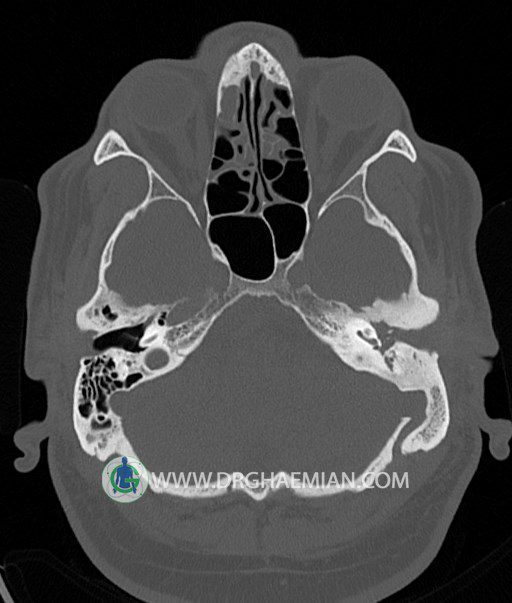

سی تی اسکن گوش داخلی به رادیولوژیست اجازه می دهد تا سطوح مختلف، یا اسلایس هایی از استخوان های که از جمجه به گوش می روند را از طریق امواج ایکس چرخشی مشاهده کند. در این کیس اودیت مدیا، ماستوئیدیت مزمن، اوتیت خارجی، انحراف سپتوم بینی، کونکا بولوزا و افزایش ضخامت سینوس ها مشاهده می شود.

در HRCT از استخوان تمپورال با مقاطع آگزيال ، ساژيتال و کرونال ظريف ( 0.6 mm ) :

– انحراف سپتوم مياني بيني به راست

– کونکا بولوزا در کونکاي مياني چپ و

– افزايش ضخامت مخاطي در سينوس هاي اتموئيد و ماگزيلاري

اپاسيته